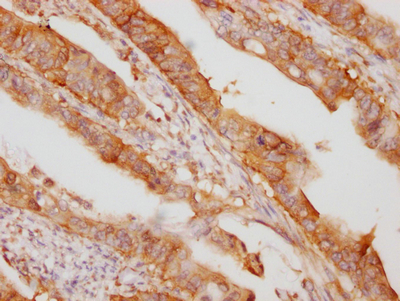

IHC image of CSB-RA932542A0HU diluted at 1:100 and staining in paraffin-embedded human colon cancer performed on a Leica BondTM system. After dewaxing and hydration, antigen retrieval was mediated by high pressure in a citrate buffer (pH 6.0). Section was blocked with 10% normal goat serum 30min at RT. Then primary antibody (1% BSA) was incubated at 4℃ overnight. The primary is detected by a Goat anti-rabbit IgG polymer labeled by HRP and visualized using 0.05% DAB.